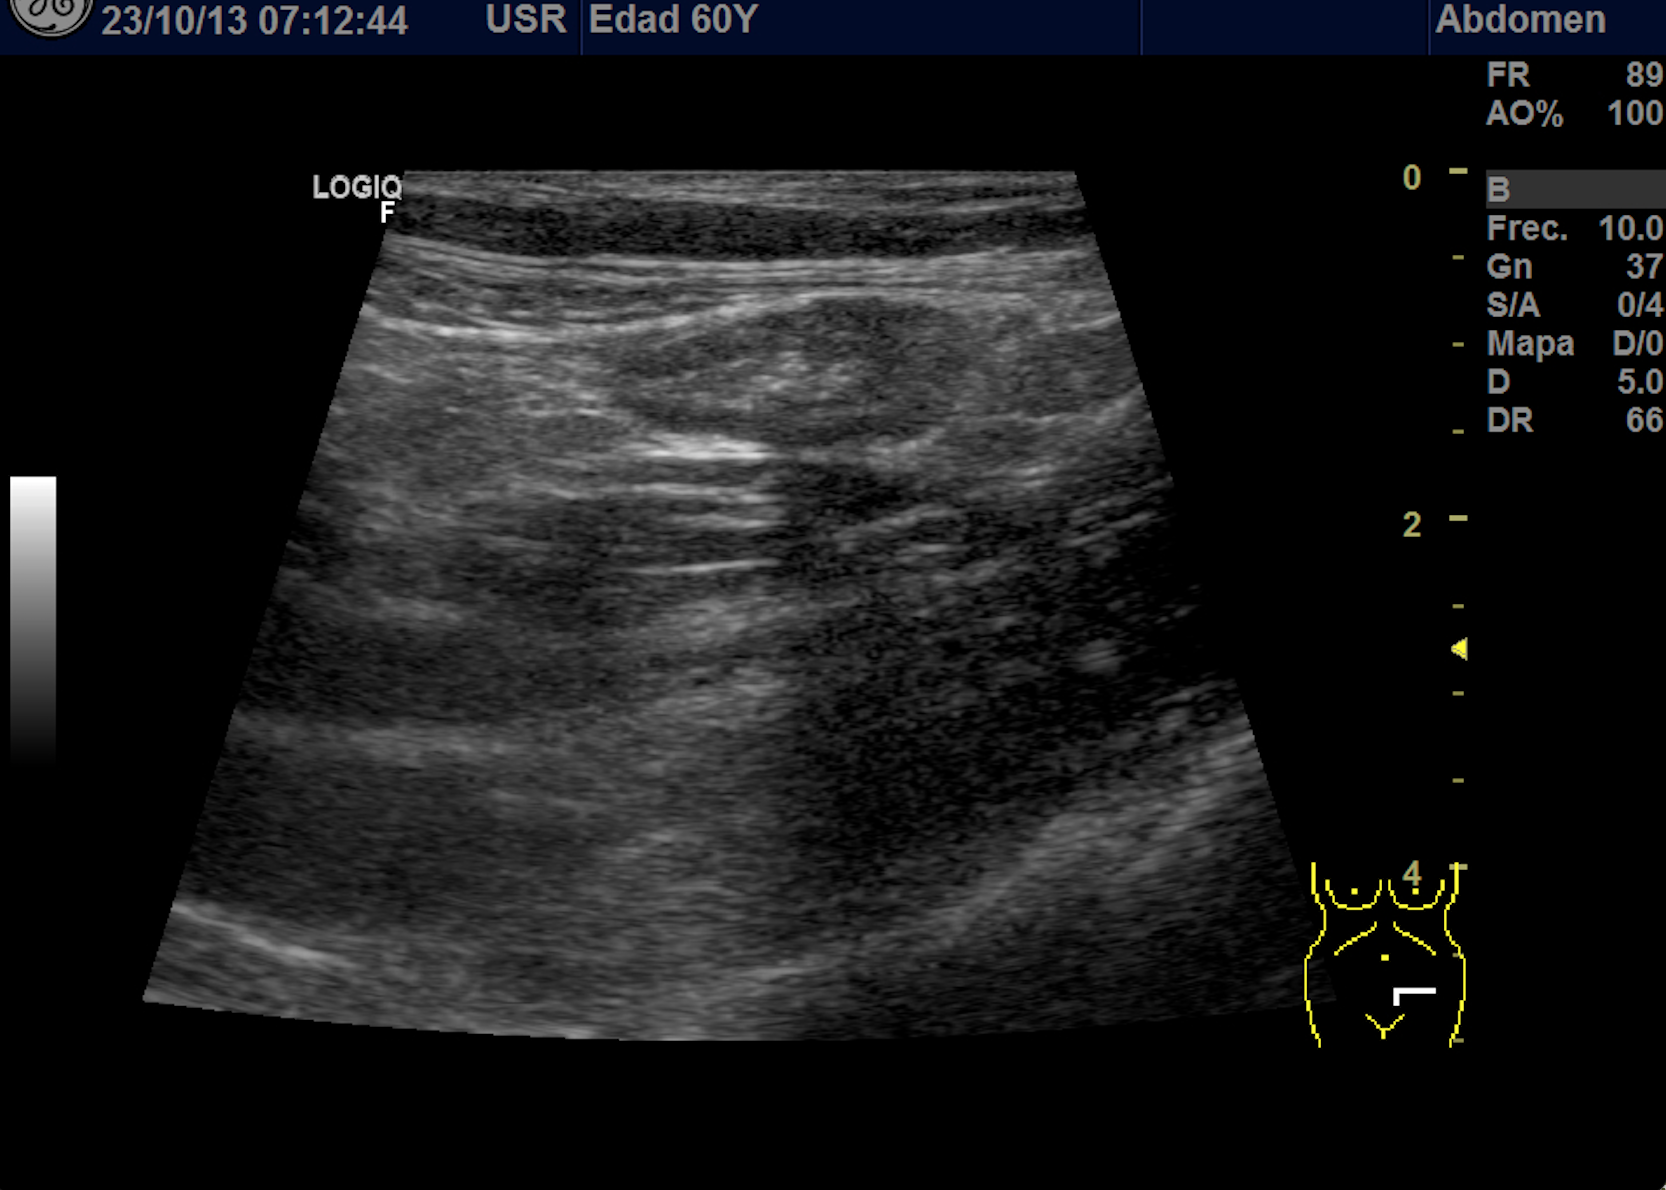

Hallazgos ecográficos

Se explora FII-hipogastrio y en el punto de más dolor se observa engrosamiento de asas de intestino grueso sin peristaltismo y con signos de edema de la grasa adyacente. No líquido libre.

También se realiza ecografia en urgencias del hospital.

En el hospital se realiza una nueva ecografía en el servicio de radiología confirmando el diagnóstico de sospecha: diverticulitis aguda en sigma distal sin datos de complicación. Hinchey 1A.